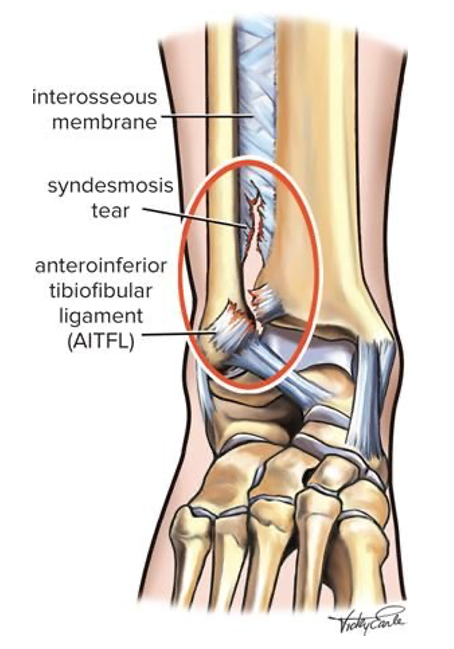

A lesão da sindesmose do tornozelo, também conhecida como entorse alta do tornozelo, é uma condição incomum que afeta a estrutura fibrosa que conecta os ossos da tíbia e do perónio.

A lesão da sindesmose do tornozelo geralmente ocorre devido a uma força rotacional ou um trauma direto que provoca uma separação anormal entre a tíbia e o peróneo. Tipicamente, resultam de uma rotação externa forçada do pé com um tornozelo em dorsiflexão, como em desportos que envolvem mudanças rápidas de direção, como futebol, basquetebol, e rugby.